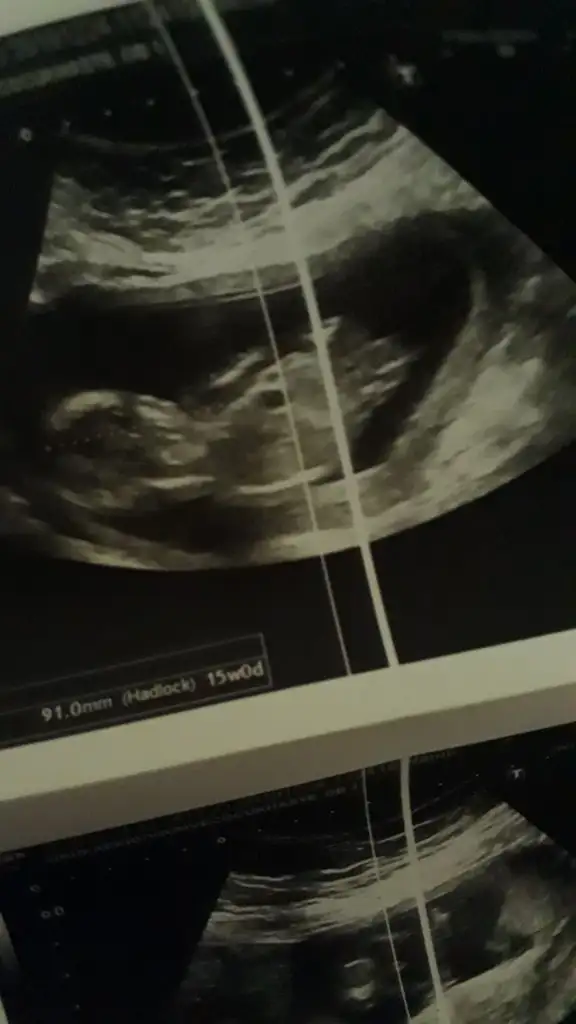

15 hafta usg nubu dik görünüyor sanki erkek gibi 11yada 12 hafta usg varmıSizce nedir?

Evet bildiniz15 hafta usg nubu dik görünüyor sanki erkek gibi 11yada 12 hafta usg varmı